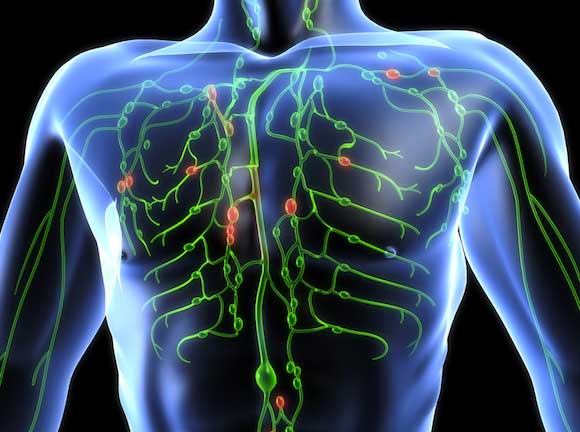

Изображения и схемы: как выглядит лимфа